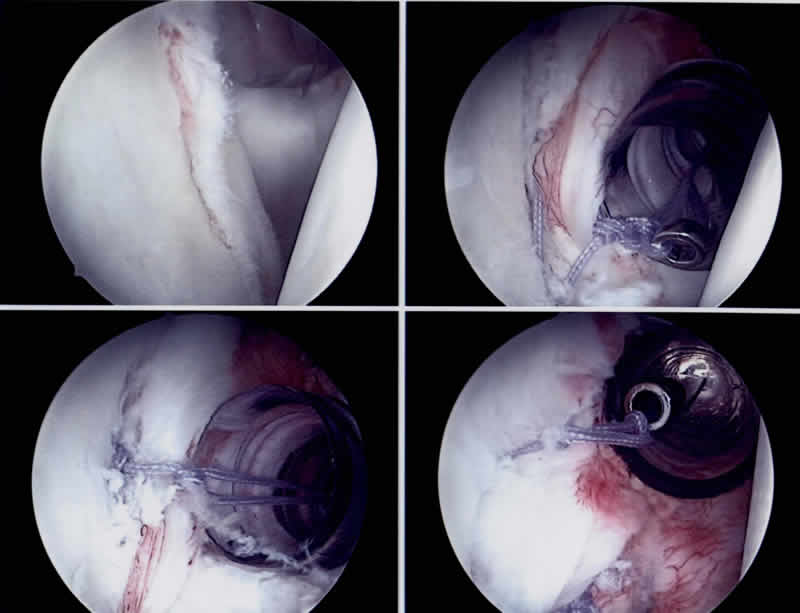

Neutral Wedge Kissen

Die offene Operation andererseits offeriert höhere Stabilitätssicherheit im Langzeitverlauf (ca.5% Reluxationen gegenüber ca.10-15% bei der Anwendung der arthroskopischen Technik). Sie wird jedoch, im Unterschied zur Arthroskopie, mit dem Nachteil erkauft, bei operativen Zugangsweg zum Gelenk eine Sehne (Subscapularissehne) ablösen und refixieren zu müssen. Die Heilungszeit des Instabilitätsschadens ist aber bei beiden Methoden identisch. Arbeitsunfähigkeit, Sportkarenz sowie mögliche Komplikationen sind individuell verschieden und bilden Gegenstand unseres üblichen präoperativen Aufklärungsgespräches. Die Nachbehandlungsphase beträgt zwischen 4-6 Monaten, in dieser Zeit erfolgt eine standardisierte Physiotherapie und ein Neutral Wedge Kissen muss in den ersten 6 Wochen getragen werden.